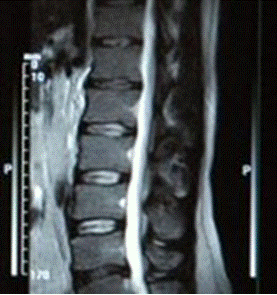

КТ позвоночника: Понимание и диагностика